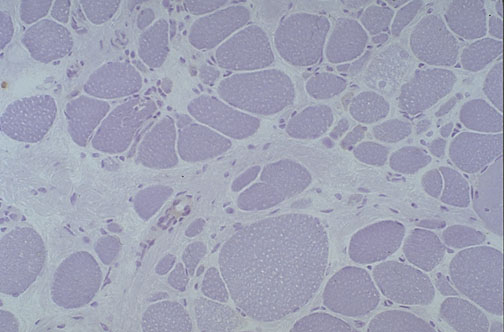

This immunoperoxidase stain utilizes antibody to the muscle protein called dystrophin, which is absent in this patient with Duchenne muscular dystrophy, because the normal gene on the X chromosome is not present.